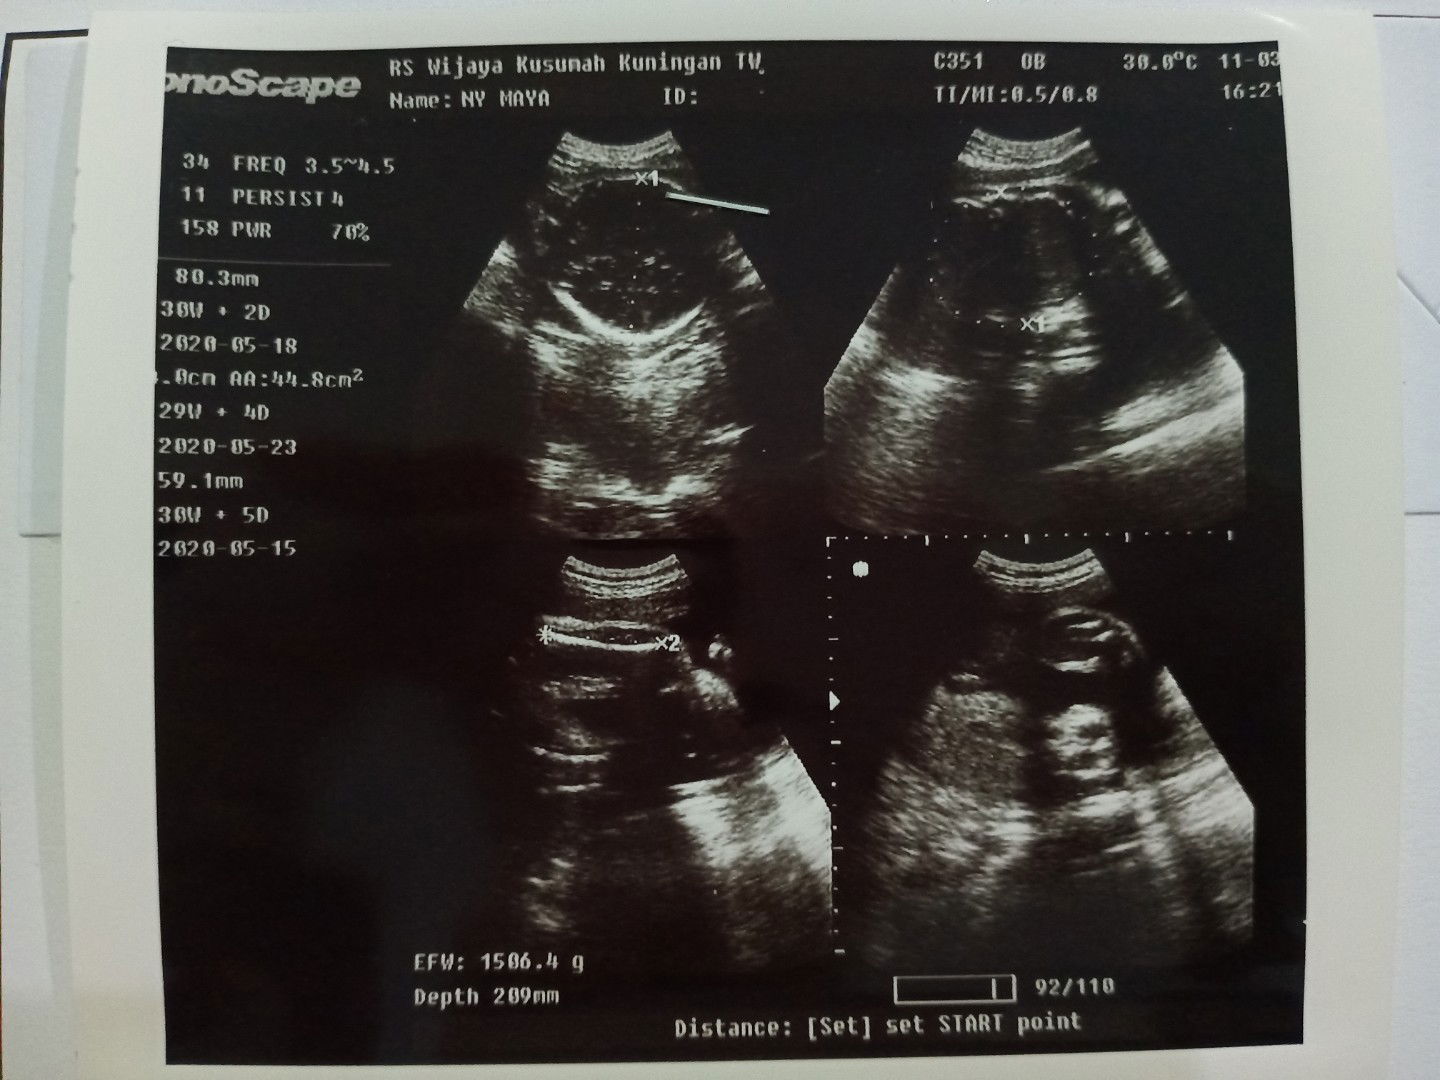

USG

Bund, usia kehamilan 31mgg dengan bbj 1,5 itu masih kurang ya ? Kira2 biar cepet nambah bbj dengan mengonsumsi apa aja ?